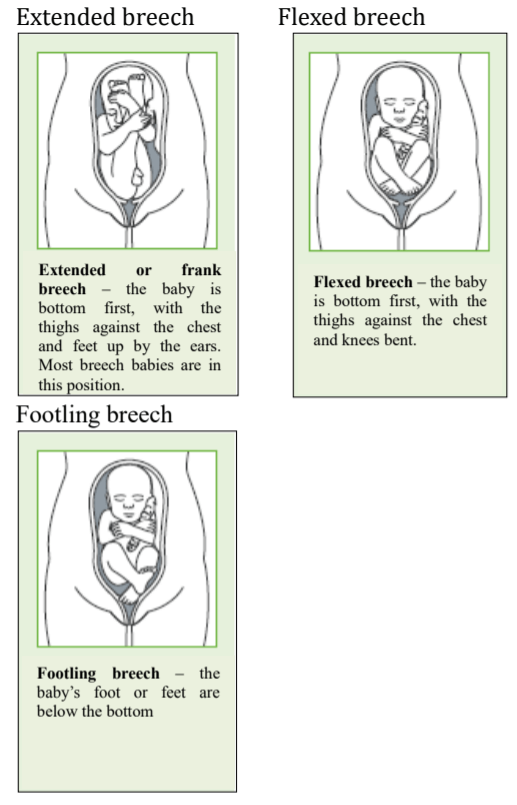

What are the breech positions?